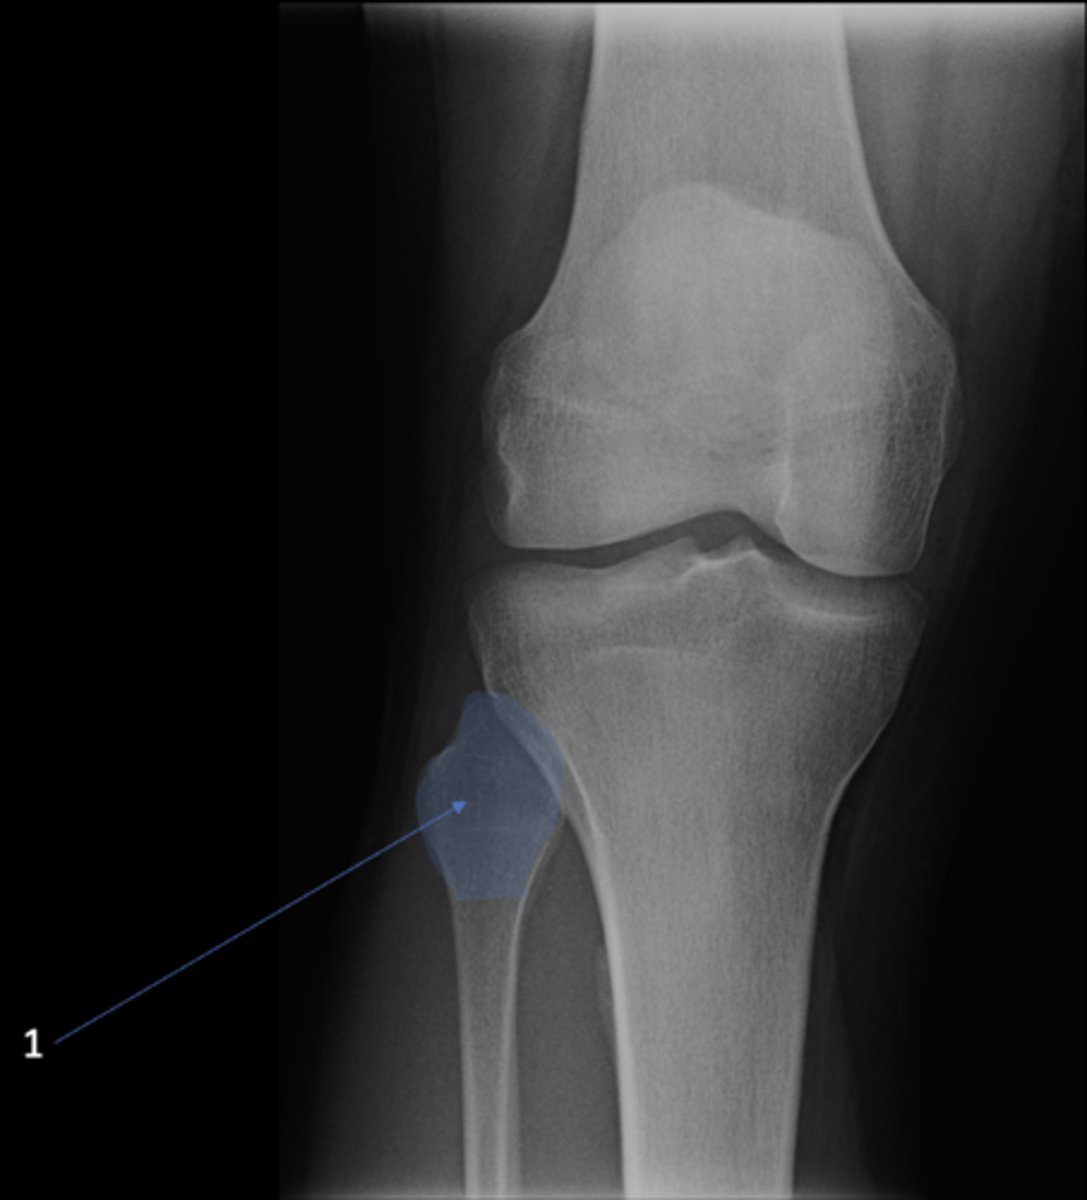

49

New cards

Fibular head

ID 1

67

Right lateral knee

View?

<p>View?</p>

68

Tibial tuberosity

ID 19

<p>ID 19</p>

69

Intercondylar eminence

ID 20

<p>ID 20</p>

70

Both tibial condyles

ID 21

<p>ID 21</p>

71

ID 22

<p>ID 22</p>

72

Apex of patella

ID 24

<p>ID 24</p>

73

Superior aspect of patella

ID 25

<p>ID 25</p>

74

Ludloff's spot/patch

ID 27

<p>ID 27</p>

75

Apex of fibular head

ID 28

<p>ID 28</p>